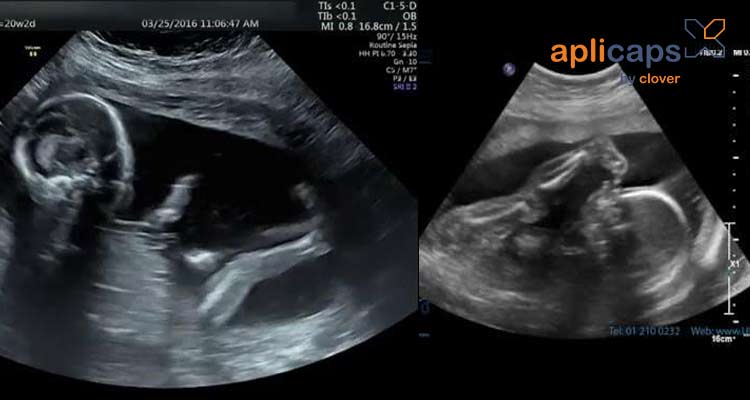

Hình ảnh siêu âm thai nhi 20 tuần khoẻ mạnh

Khi siêu âm thai ở tuần 20 mẹ có thể biết rõ hơn về em bé của mình có đang phát triển khỏe mạnh không. Bác sĩ thông qua siêu âm sẽ kiểm tra được tất cả bộ phận của thai nhi và các chỉ số cần thiết.